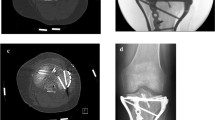

The paired specimens (n = 24) originated from eight male and four female donors(Fig. 1). Mean donor age was 79 years (range 66–99). The peroneus brevis muscle was visualized through a lateral incision, then it was carefully dissected from its origin and followed distally to the insertion at the proximal aspect of the fifth metatarsal [18]. Care was taken to prepare the whole muscle belly with the intact tendon. The PBT insertion was not touched, and the fifth metatarsal was disarticulated from surrounding joints and liberated from soft tissue. Specimens were kept moist with saline solution to prevent tissue desiccation throughout the preparation process. Each specimen was screened for any evidence of previous open peroneal tendon surgery or Jones fracture fixation. Following inspection of the specimens, all pairs proved valid for the study and thereafter were assigned to two matched pair groups comprising an equal number of left and right feet for Jones fracture creation. The fifth metatarsal bone was distally fixed in a padded machine vise during fracture creation and preparation for intramedullary screw fixation (Fig. 2). A longitudinal line was drawn on the metatarsal in order to check for the rotational alignment. To simulate a Jones fracture (zone II), a complete transverse fracture at the meta-diaphyseal junction at the distal aspect of the fourth to fifth intermetatarsal articular facet was created with an oscillating saw. The proximal part of the bone was held in place with a small forceps during intramedullary screw preparation and placement. One group underwent intramedullary fixation with a Jones fracture-specific screw (Jones Screw; Arthrex Inc., Naples FL, USA) (JFXS group), while the other group was stabilized with a conventional cannulated headless compression screw (HCS; DePuySynthes, Solothurn, Switzerland) (HCS group). Screw size was determined upon the “fit and fill” principle. The intramedullary screw had to “fit and fill” the medullary canal with the threads across the fracture site. HCS were available in diameters 4.5-mm and 6.5-mm, and Jones Screws were used in diameters 4.5-mm and 6.0-mm. Small matched pair specimens (3/12) received 4.5-mm JFXS or HCS, and large specimen pairs (9/12) received 6.0-mm JFXS or 6.5-mm HCS.

Intramedullary screw fixation technique. Intramedullary screw fixation is schematically outlined on a left fifth metatarsal using a 4.5-mm solid fracture specific screw (Jones fracture screw, Arthrex Inc., Naples, FL). In the first step (1), the fifth metatarsal bone was distally fixed in a padded machine vise. The bone and the peroneus brevis muscle were kept moist during preparation. (2) Then a complete Jones fracture at the meta-diaphyseal junction at the distal aspect of the 4th–5th intermetatarsal articular facet (green line) was created by the use of an oscillating saw. A small forceps fixed and held the proximal fragment in place. In the next step, preparation for intramedullary screw fixation started by marking the entry point for the screw. (3) In a proximal dorsal view, the entry point is located “high and inside”, lateral to the cubometatarsal articular surface [5]. Anatomic studies described the ideal starting point 10.5-mm dorsal to the palpable inferior margin of the proximal tuberosity, and just medial to the peroneus brevis insertion. In a craniocaudal orientation the entry point is approximately 5.3-mm medial to the palpable lateral aspect of the tuberosity. [34] (4) A 2.0-mm guide wire is drilled into the metatarsal aiming for the straight part of the intramedullary canal. Afterwards, cannulated drilling with a 3.5-mm drill was performed followed by taping, starting with a 4.5-mm tap. The threads should tightly engage with the endosteal bone of the intramedullary canal. If the tap felt undersized, the next size was used (i.e., 6.0 for JFXS and 6.5 for HCS preparation). During taping, the appropriate screw size and length were measured by tactile feedback and by visual inspection superimposing the screw over the metatarsal. Screw length was determined as approximately 70% of the total length of the fifth metatarsal. Screw threads must cross the fracture line. (5) Finally, the guide wire was removed for solid screw (JFXS) insertion and the appropriate screw was inserted by hand. (6) Optimal screw size implantation was verified via X-ray control. Schematic view from medial.

Bony cut out of the proximal screw head was the most common mode of failure among HCS constructs (n = 6; 50%), followed by fracture of the metatarsal at the level of embedding in the steel cup (n = 4; 33%) (Supplementary Video 1). In JFXS constructs, the most common mode of failure was classified as fracture of the metatarsal at the steel cup (n = 5; 50%) followed by a bony cut out of the screw head (n = 3; 30%) (Fig. 5). No screw bending or screw breakage was observed.